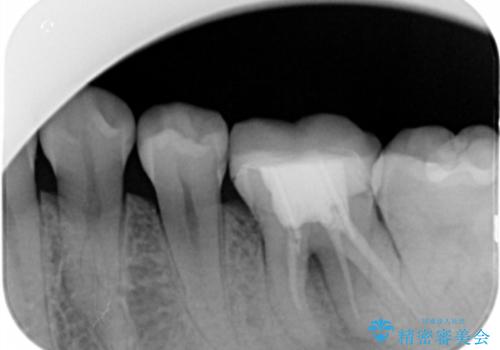

- 左下大臼歯の歯肉に腫れと痛みが繰り返し起こっているので治療を希望し来院された患者様です。

既に治療されている歯でしたが根尖部に病巣が確認出来たので、精密根管治療とクラウンの再治療が必要と判断されました。

精密根管治療を行なったことで病巣は消失し、腫れや痛みは再発することなく経過は良好です。